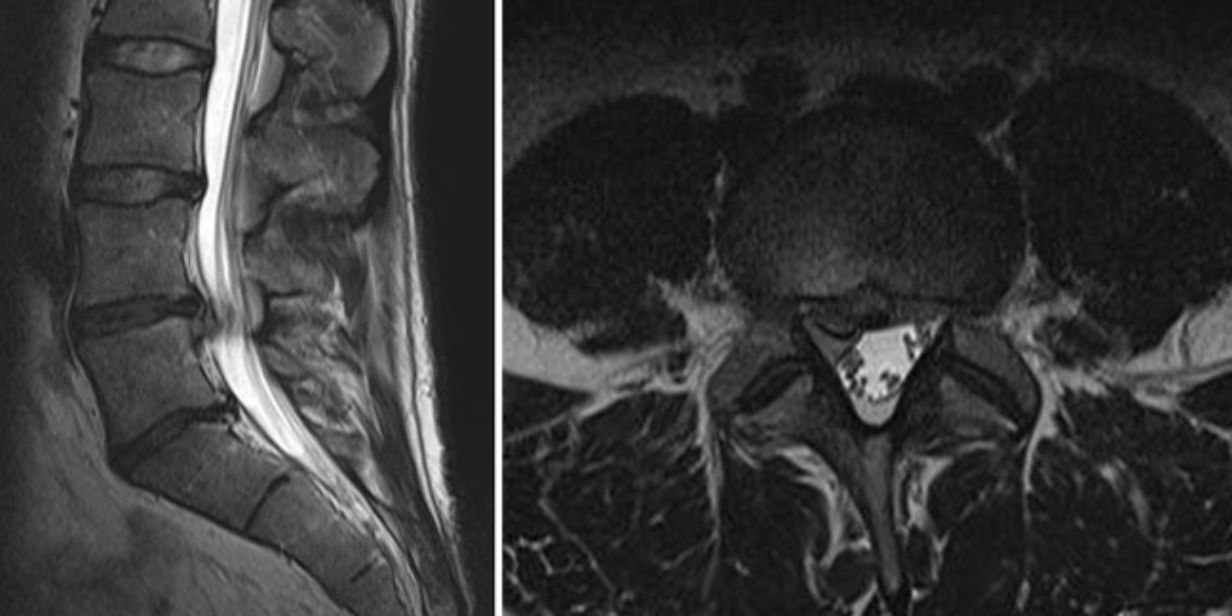

Bandscheibenvorfall Symptome, Ursachen und Behandlung Heilpraxis So stellt der Arzt die Diagnose Bandscheibenvorfall Wie merkt man, dass man einen Bandscheibenvorfall hat? Lumedis - Ihre Bandscheibenspezialisten Ein Bandscheibenvorfall kann das Leben erheblich beeinträchtigen und verursacht oft Kribbeln, Taubheit oder starke Schmerzen "Auf dem MRT kann man ganz klar einen Bandscheibenvorfall erkennen." sagt Thomas, während er mir seine Aufnahmen zeigt

Source: lowdlifeytj.pages.dev Bandscheibenvorfall erkennen Symptome & Behandlung , Oft trifft es Lendenwirbelsäule (LWS) oder Halswirbelsäule (HWS) "Auf dem MRT kann man ganz klar einen Bandscheibenvorfall erkennen." sagt Thomas, während er mir seine Aufnahmen zeigt

Source: dexnethsa.pages.dev Der Bandscheibenvorfall (Teil 1) I 006 Körperkunde , "Auf dem MRT kann man ganz klar einen Bandscheibenvorfall erkennen." sagt Thomas, während er mir seine Aufnahmen zeigt Oft trifft es Lendenwirbelsäule (LWS) oder Halswirbelsäule (HWS)